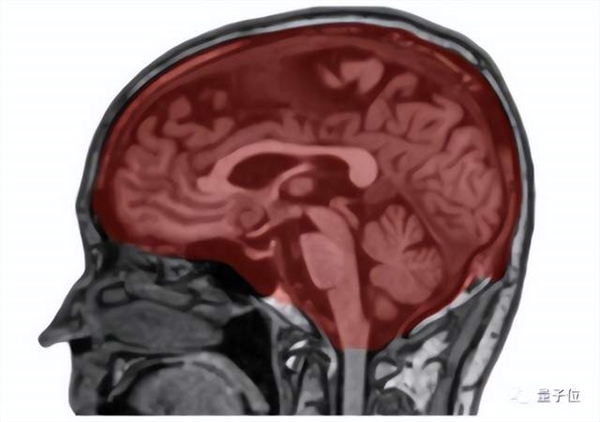

△脑体积分割结果

来看看两位61岁女性的核磁共振成像,左边人的内脏脂肪和皮下脂肪含量均较高,右边这位属于正常水平。可以明显看出,左边人的脑体积要比右边人的小,具体表现为脑室扩大、沟回增宽。

△高体脂脑体积缩小示例